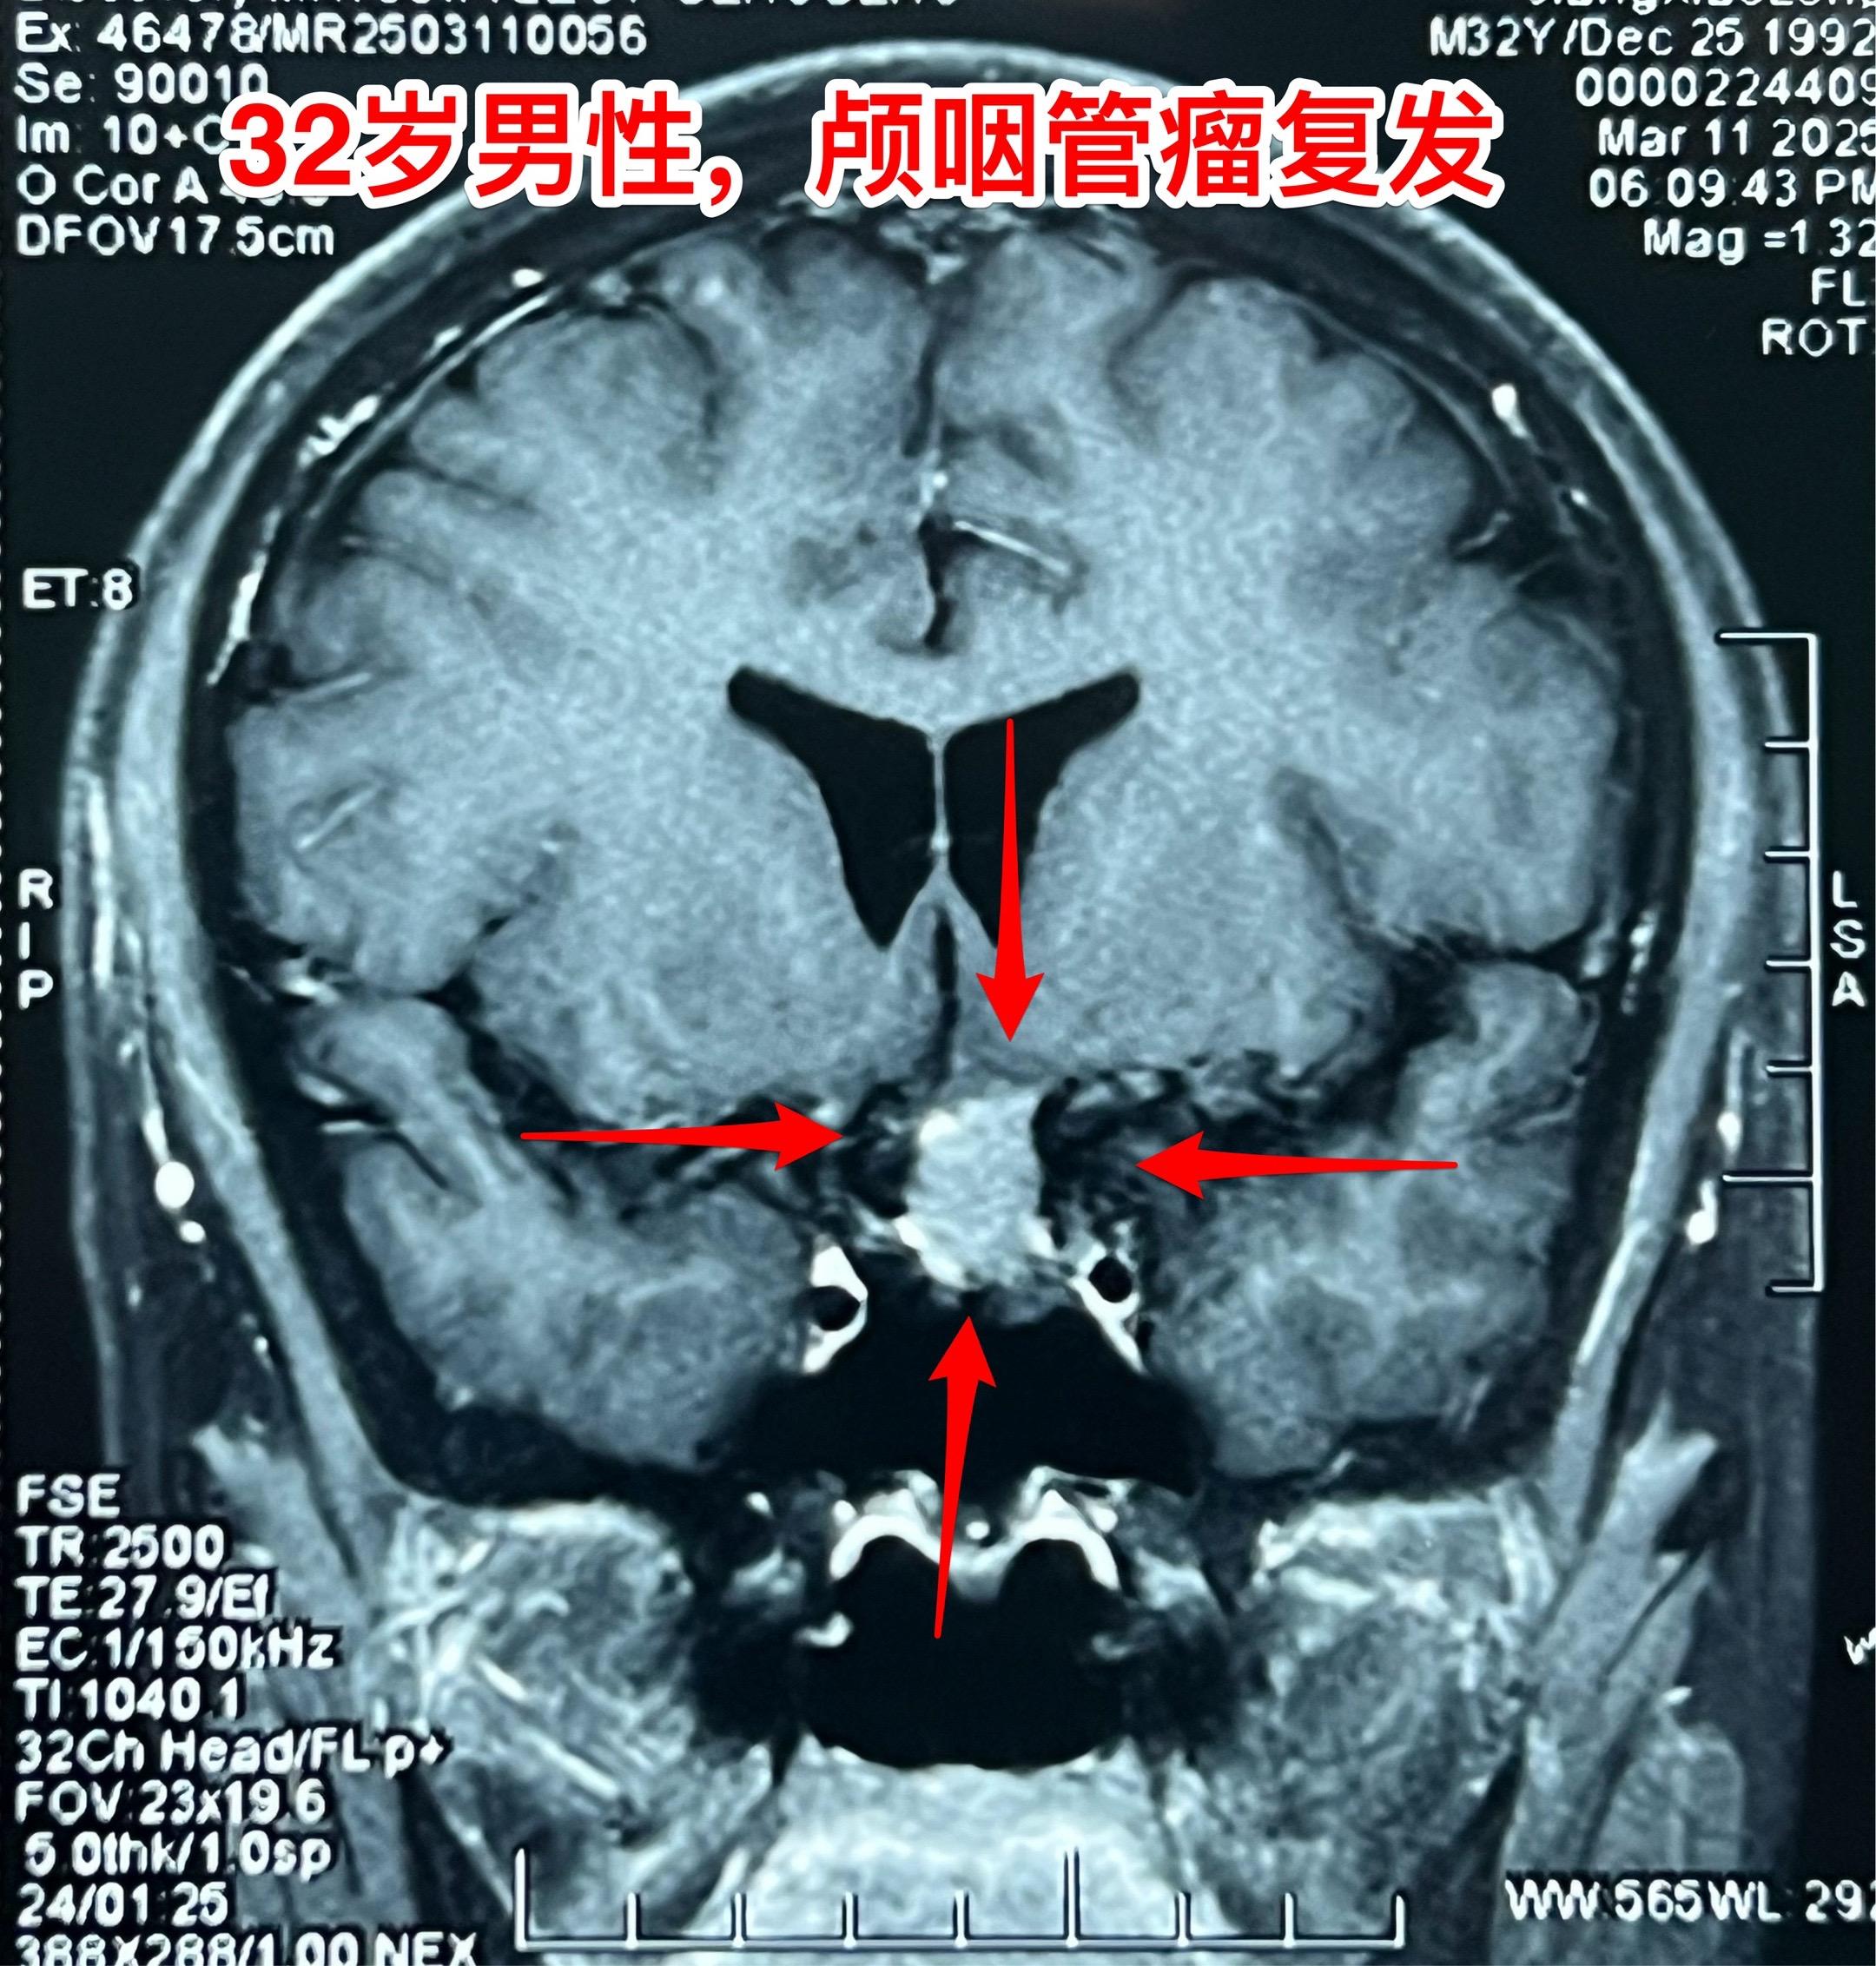

3月28日两个颅咽管瘤手术 两个都是经鼻手术手术后复发的颅咽管瘤手术。我采用了开颅手术。 第一个是64岁山西人,颅咽管瘤手术后再次出现视力下降,复查磁共振显示肿瘤复发。肿瘤是囊性乳头型颅咽管瘤,没有钙化。 第二个是32岁的湖南小伙。肿瘤有钙化。 今年春节后我科颅咽管瘤中经鼻手术后复发的病人比例明显升高了。与近十年经鼻内镜手术广泛开展是有关系。 无论是哪种手术方案,只有效果好、复发率低,病人才会满意。